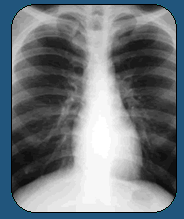

Juarez' strain of TB puzzled doctors. He had never

had TB before. Where did he pick it up? Had he passed

it on? And could they stop it before it killed him?

At first, mainstream doctors tried to treat him. But

the disease had already gnawed a golf-ball-sized hole

into his right lung.

When put side by side, his CAT scans from before and

after treatment are hard to believe. The dark hole

is gone, and only a small white scar tattoos his lung.